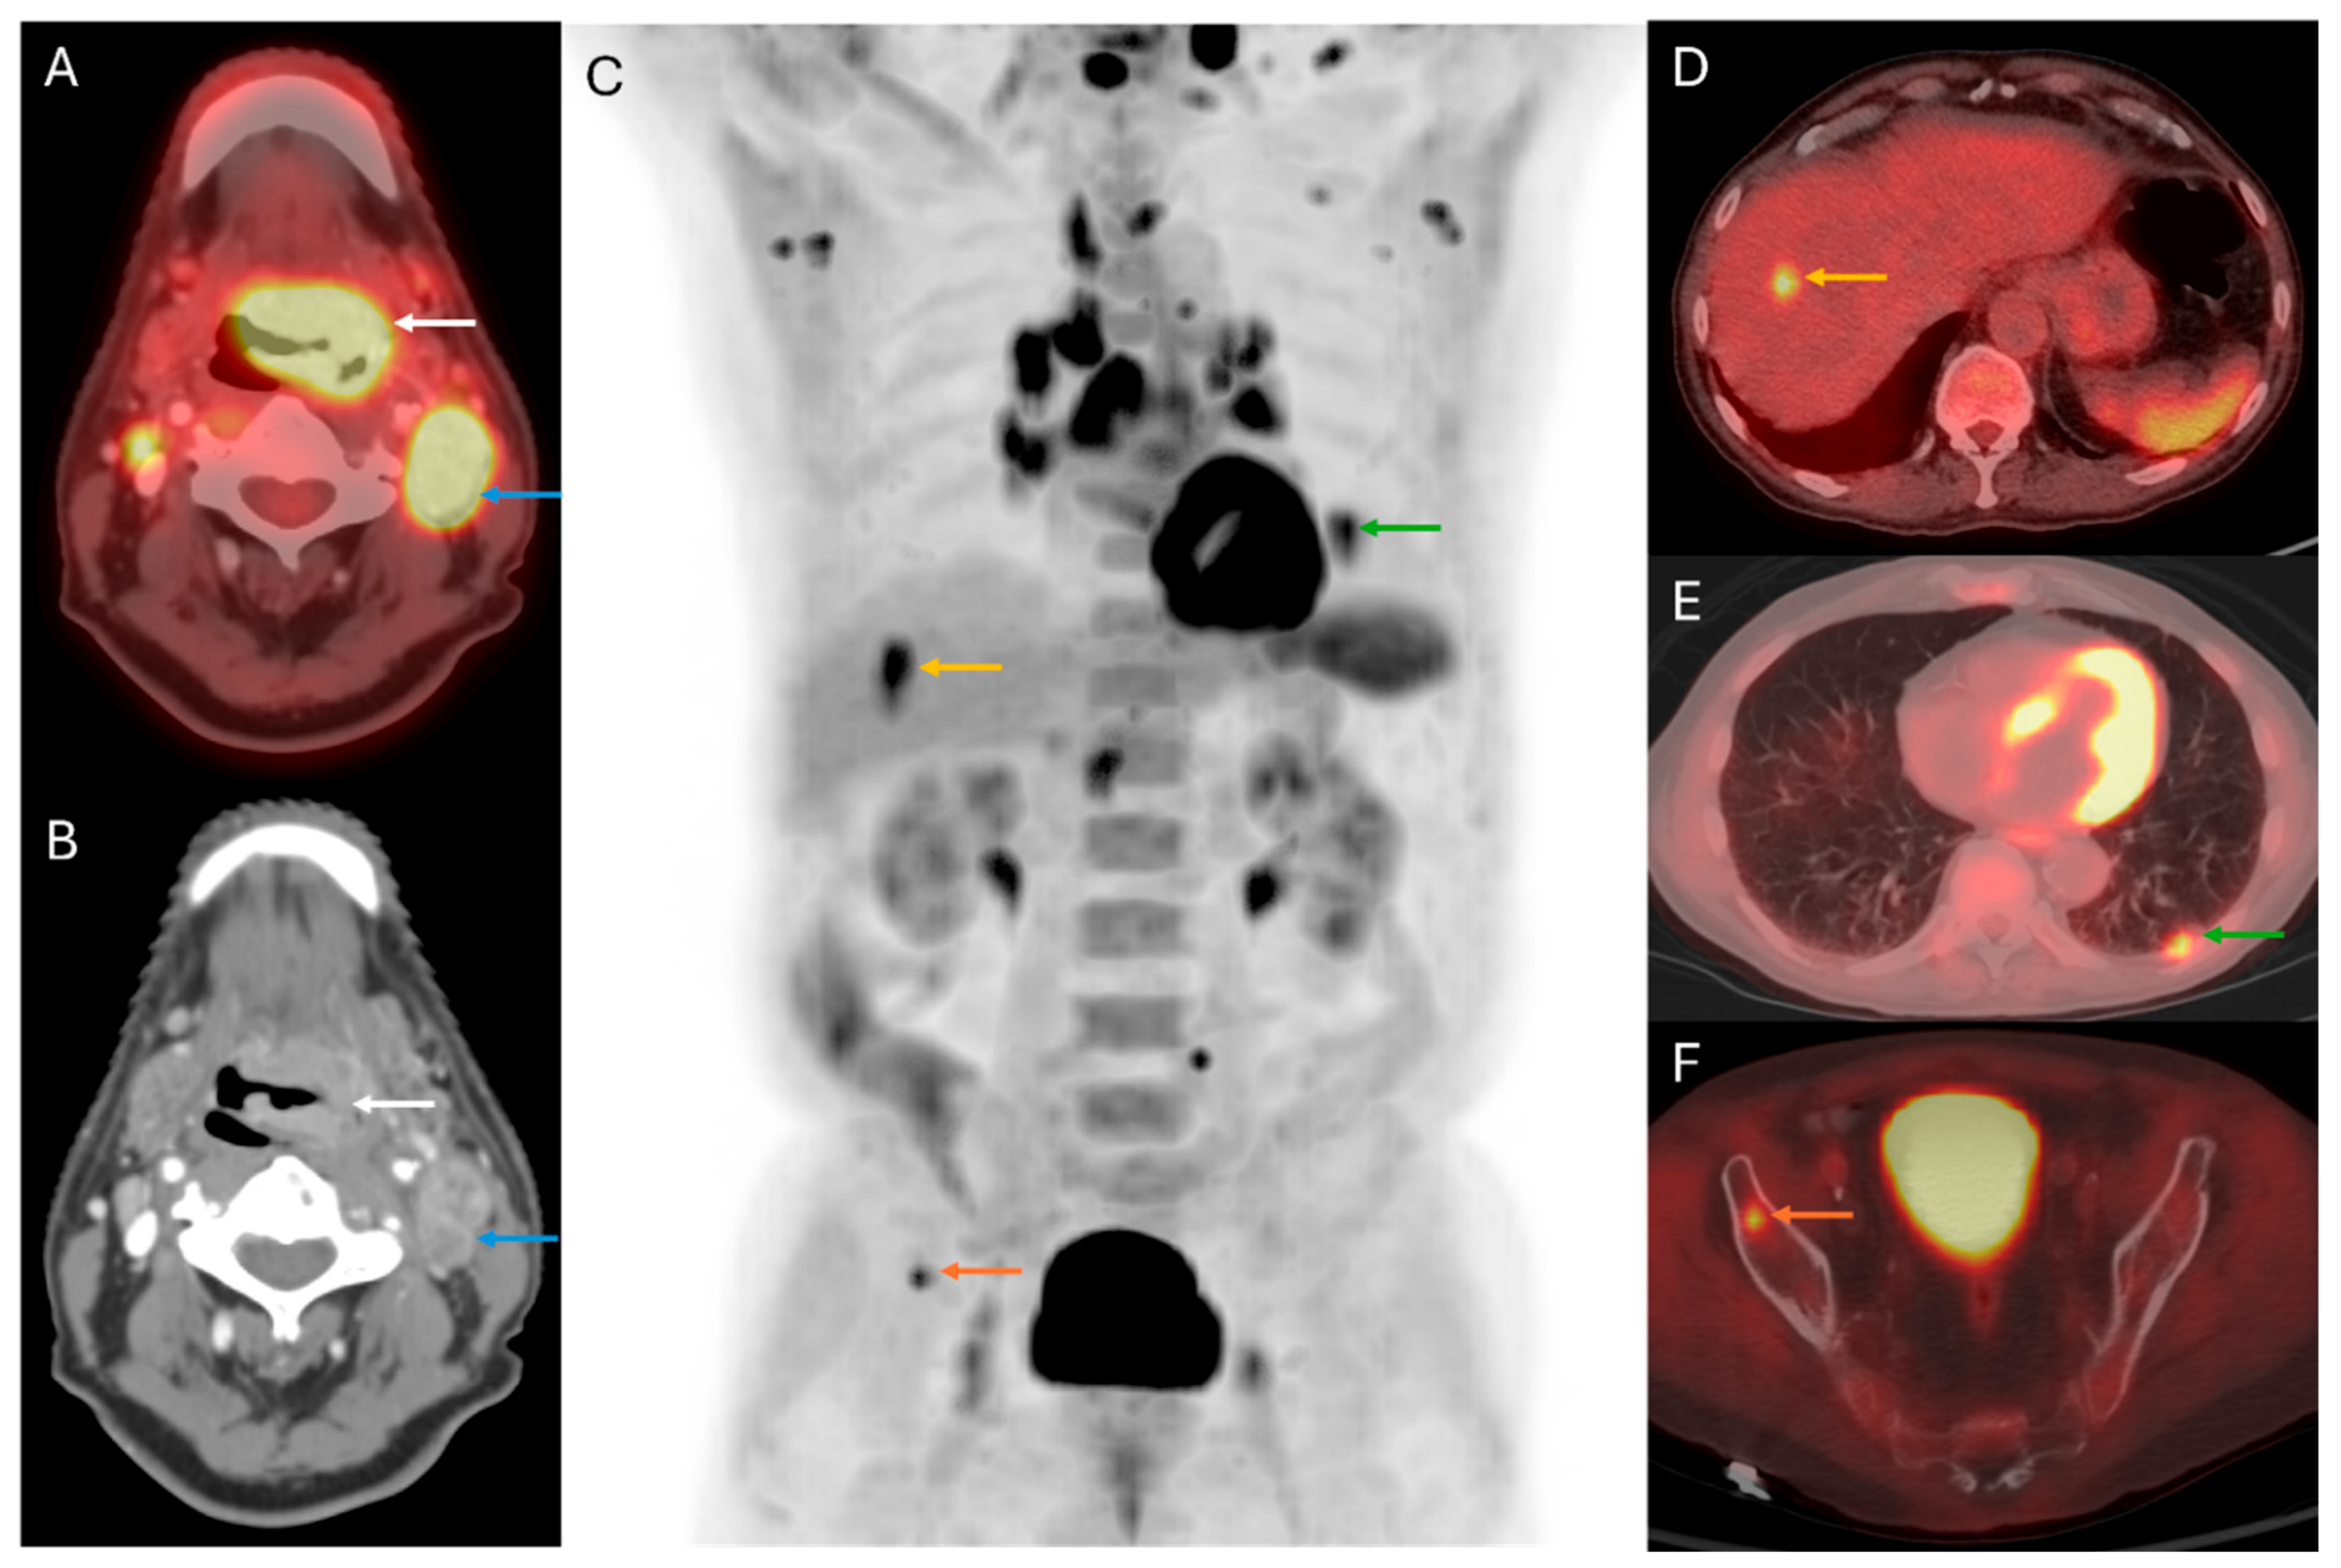

5. Distant Disease Detection

3. Primary Tumor Staging